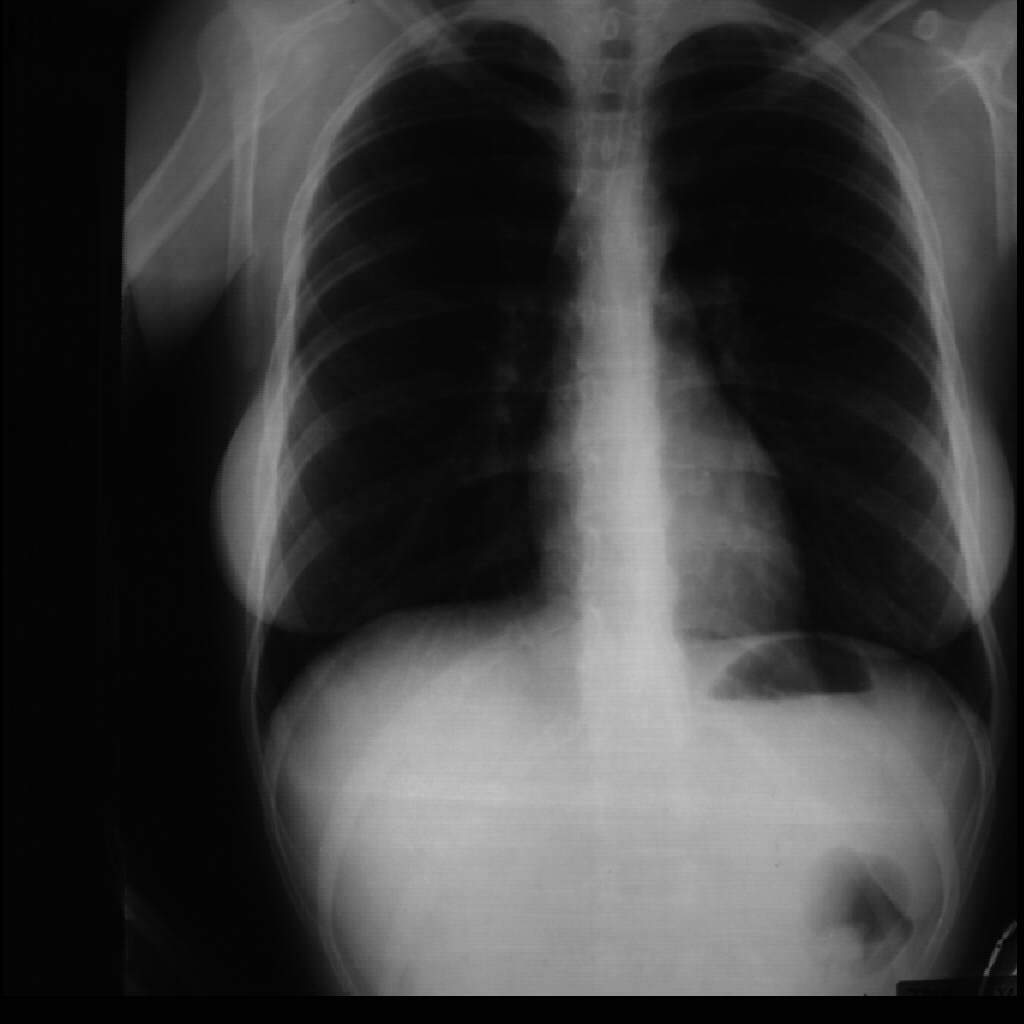

Imagen de una radiografía en la que existen zonas oscuras porco visibles